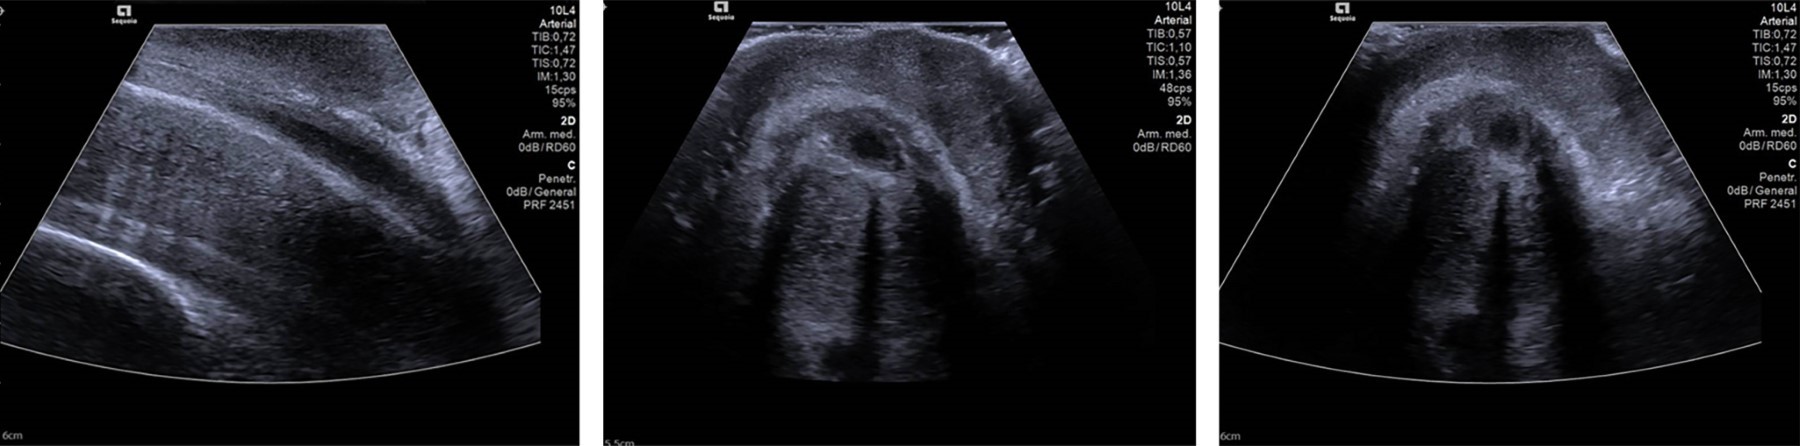

En la exploración física se observó una erección dolorosa sin pulsos palpables, lo que condujo a la realización de una gasometría arterial de la arteria cavernosa y un ultrasonido Doppler arterial de pene que confirmaron la presencia de priapismo con flujo ausente debido a trombosis en la arteria cavernosa (Figura 1). Se decidió ingresar al paciente al servicio de cirugía para el drenaje de los cuerpos cavernosos, sin embargo, al no lograr los resultados esperados debido a la vasodilatación y ausencia de flujo, se realizó una segunda intervención, consistente en un shunt cavernoso-esponjoso anterior y posterior bilateral, junto con peneplastia, lo que resultó en una mejoría significativa de los síntomas y permitió su alta hospitalaria.

Figura 1